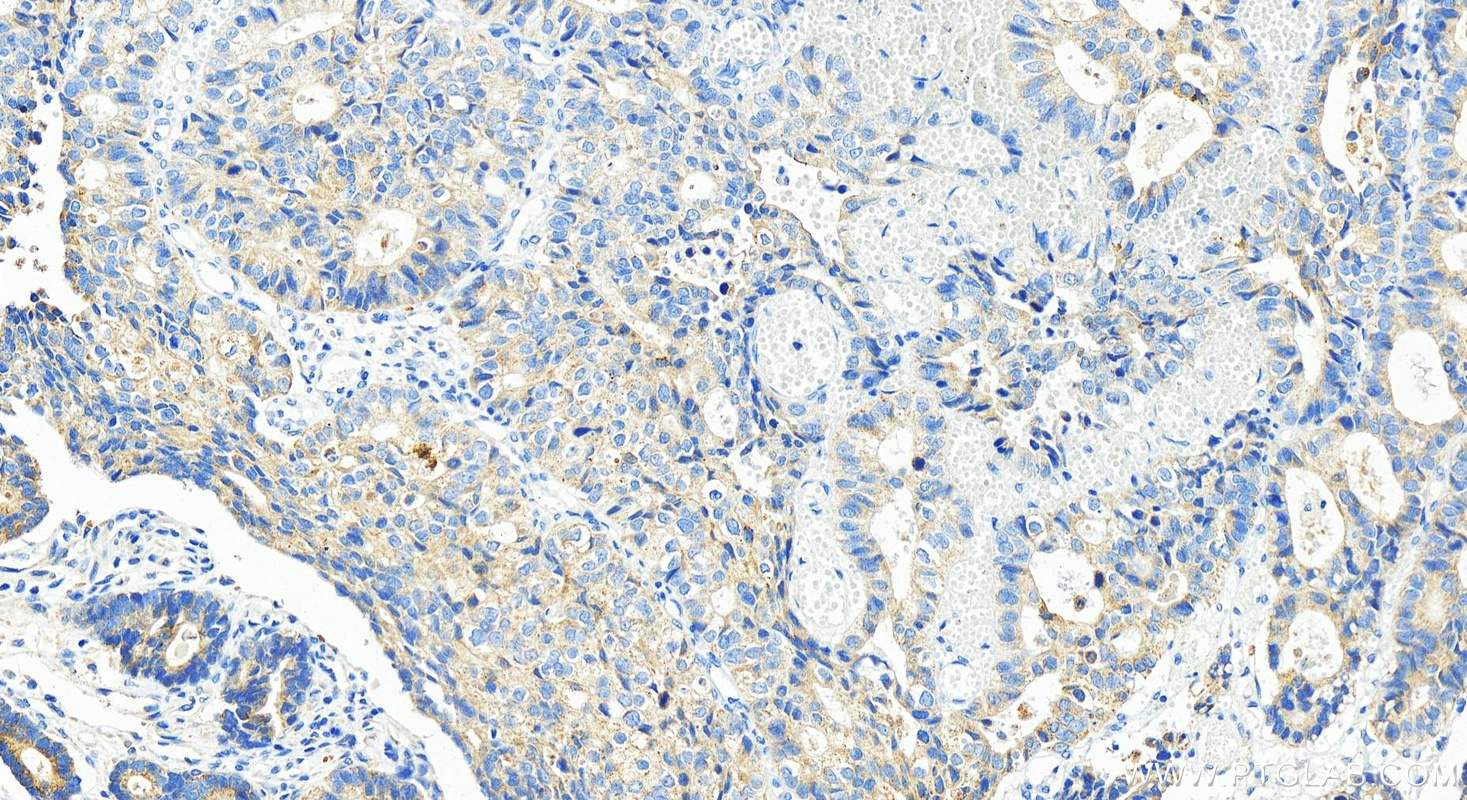

| Positive IHC detected in | human stomach cancer tissue Note: suggested antigen retrieval with TE buffer pH 9.0; (*) Alternatively, antigen retrieval may be performed with citrate buffer pH 6.0 |

| Immunohistochemistry (IHC) | IHC : 1:400-1:1600 |